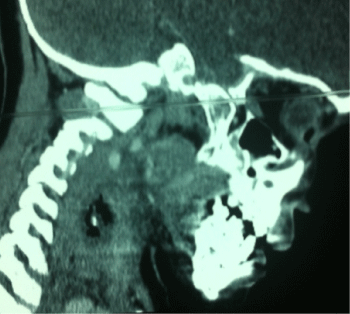

Neck x-ray revealed linear radio opacity suggestive of a foreign body at the level of C5-6 vertebrae. A computed tomography (CT) scan was then done that showed a 2cm long metallic foreign body in the subcutaneous tissues of neck at the level of C5-6 vertebrae (Figure 1,2).

Figure 2: CT sagittal image of neck showing the metallic foreign body.